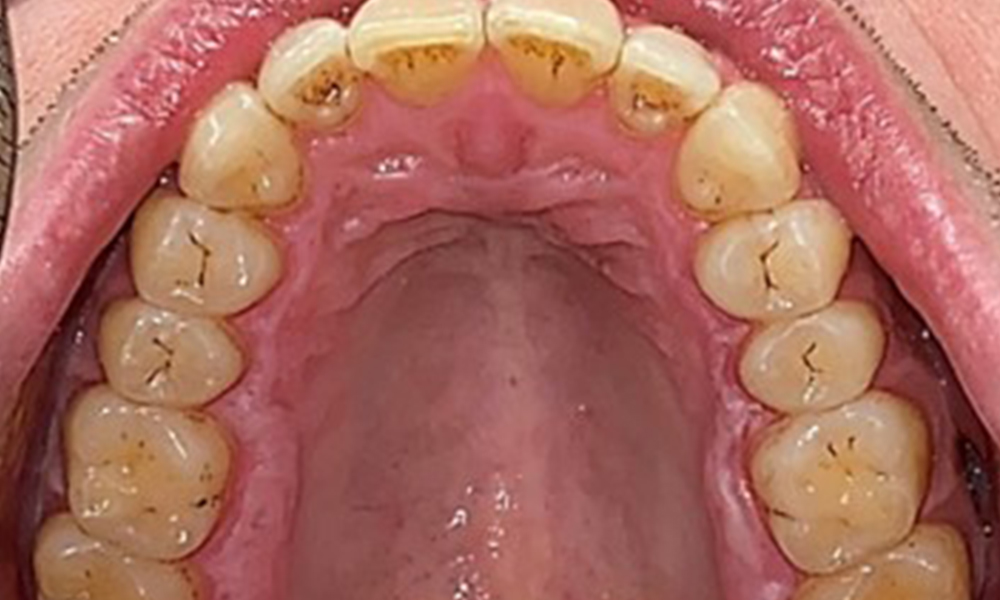

Okklusalansicht Oberkiefer

Abb. 3: Okklusalansicht Oberkiefer, © Dr. R. Krapf

Extraoral sind keine pathologischen Befunde festzustellen, intraoral zeigen sich bei der Frontalansicht im Bereich der keratinisierten Gingiva und am Übergang zur beweglichen Schleimhaut bräunlicheVerfärbungen (Abb. 2), welche auf den Nikotingenuss zurückzuführen sind. Am Gaumenbereich zeigen sich insbesondere im Bereich Oberkiefermolaren palatinal weißliche Schleimhautveränderungen, die ein Hinweis auf einen erhöhten Verhornungsgrad sind und ebenso auf den Nikotingenuss zurückzuführen sind. Die Zunge ist mit einem weiß-bräunlichen abwischbaren Belag versehen.

Dentaler Befund

Dental zeigt sich ein vollbezahntes Gebiss mit 28 Zähnen. Auffällig sind Erosionen und Attritionen

(Abb. 4, Abb. 5). Der Patient trägt seit vielen Jahren nachts eine Schiene mit adjustiertem Aufbiss aufgrund Bruxismus. Die Erosionen sind auf den langjährigen Konsum isotonischer Getränke zurückzuführen. Parodontaler Knochenverlust und aktive kariöse Läsionen sind nicht vorhanden.